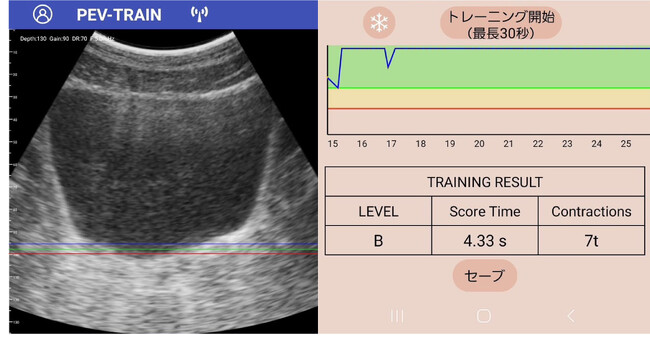

▲専用アプリで見た骨盤底筋の様子と、トレーニング結果を示すデータ

– 「アプリが自動で効果を計測」 「収縮幅」「収縮時間」を自動レコーディングし、トレーニング成果を一目で把握。